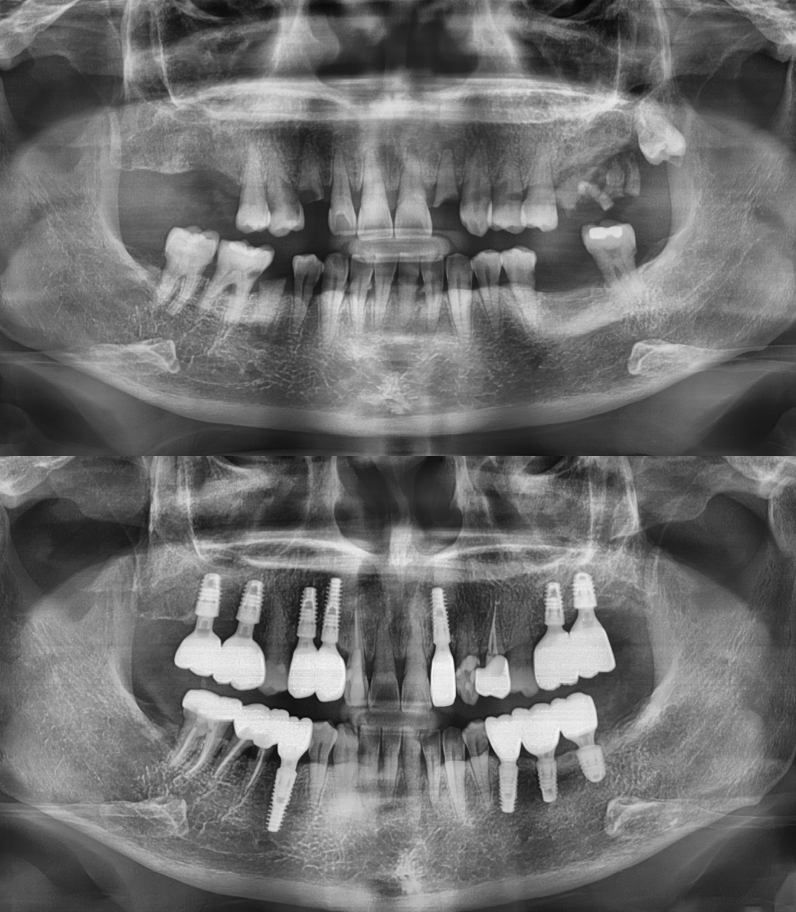

임플란트 전/후

실제 케이스

성공적인 임플란트 치료는 세밀한 분석과

그에 맞는 치료가 중요하기에

다수의 치료 경험을

보유한 의료진이 상주한 곳에서 시작하시기 바랍니다.

임플란트

환자 성함 : 강**

치료기간 : 2023.05 - 2023.12 (7개월)